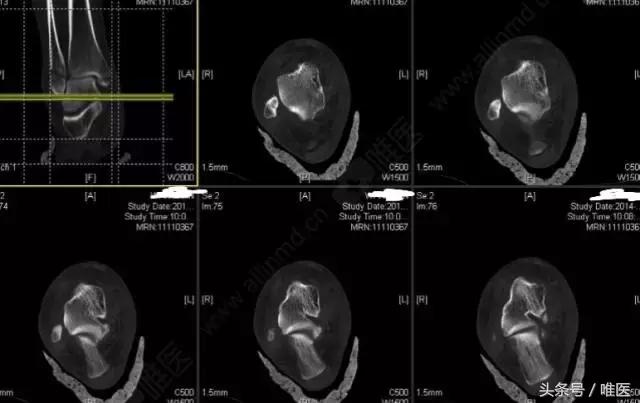

CT二维重建: 右侧踝关节骨折

L-H分型:旋后外旋型 IV度;

Danis-Webber分型:B型